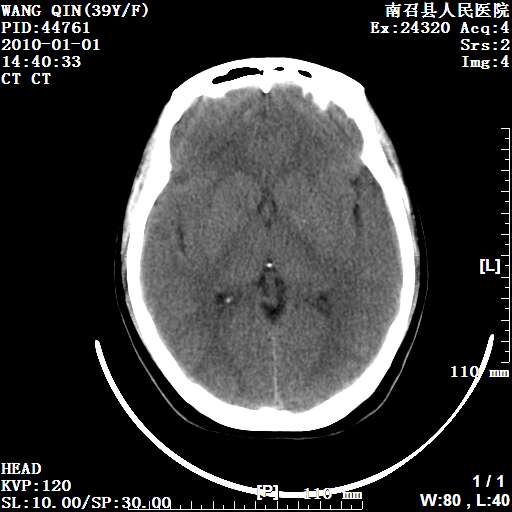

以下是引用随光逐影在2010-1-22 9:03:00的发言:[br]考虑左侧中颅窝(蝶骨翼区)脑膜瘤侵犯蝶骨翼并突入左侧眼眶。

以下是引用水过无痕在2010-1-22 14:55:00的发言:[br]一、定位:颅外占位;二、定性:恶性可能性大;三、组织来源:来源于左侧眼外直肌或其他部位;考虑为:横纹肌肉瘤>转移瘤>脑膜瘤.